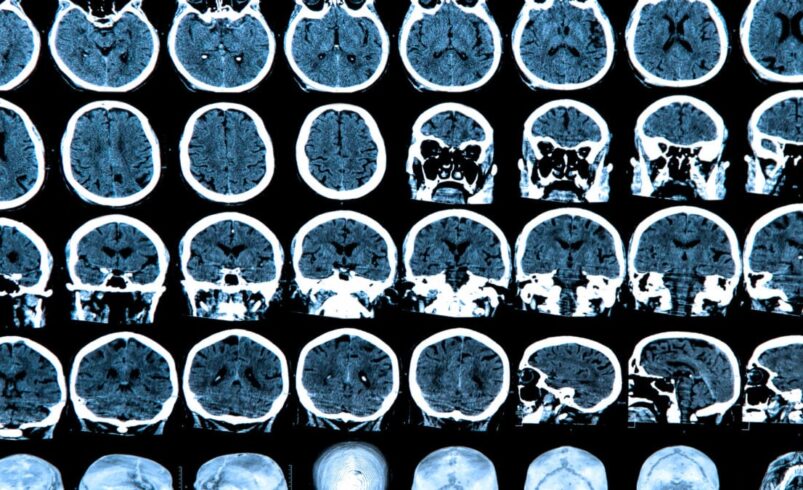

Consciousness is usually defined by neuroscientists as the ability to have subjective experience, such as the experience of tasting an apple or of seeing the redness of its skin. The leading theories of consciousness suggest that the outer layer of the human brain, called the cortex (in blue in figure 1), is fundamental to consciousness. This is mostly composed of the neocortex, which is newer in our evolutionary history.

The human subcortex (figure 1, brown/beige), underneath the neocortex, has not changed much in the last 500 million years. It is thought to be like electricity for a TV, necessary for consciousness, but not enough on its own.

There is another part of the brain that some neuroscientific theories of consciousness state is irrelevant for consciousness. This is the cerebellum, which is also older than the neocortex and looks like a little brain tucked in the back of the skull (figure 1, purple). Brain activity and brain networks are disrupted in unconsciousness (like in a coma). These changes can be seen in the cortex, subcortex, and cerebellum.